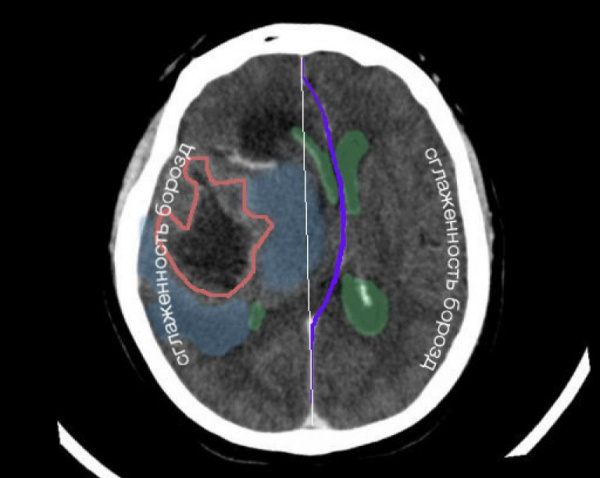

А — КТ головного мозга больного с ЧМТ. Аксиальный срез. Острая субдуральная гематома над левым полушарием (черная стрелка), срединные структуры смещены вправо на 11 мм, левый боковой желуцочек компремирован, нижний рог правого — расширен. Дислокация мозга под большой серповидный отросток (белая стрелка); б — МРТ головного мозга больного с ЧМТ. Т1-взвешенное изображение. Фронтальный срез. Острая субдуральная гематома над правым полушарием (черная стрелка), срединные структуры смещены влево на 8 мм. Дислокация мозга под большой серповидный отросток (белая стрелка). Компрессия правого бокового желудочка. Левый желудочек расширен.

А — КТ головного мозга больного с ЧМТ. Аксиальный срез. Острая эпидуральная гематома в левой теменно-затылочной области (черная стрелка), срединные структуры смещены вправо на 9 мм. Дислокация мозга под большой серповидный отросток (маленькая белая стрелка) и височно-тенториальная дислокация (большая белая стрелка); б—МРТ головного мозга больного с ЧМТ. T1-взвешенное изображение. Фронтальный срез. Хроническая субдуральная гематома над правым полушарием (черная стрелка), срединные структуры смещены влево на 8 мм. Дислокация мозга под большой серповидный отросток (маленькая белая стрелка) и височно-тенториальная дислокация (большая белая стрелка).